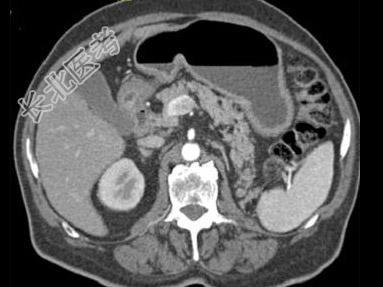

- 单项选择题根据所提供的图像,最可能的诊断是 ( )

A、胰腺脂肪瘤

B、正常胰腺

C、胰腺癌

D、胰腺转移癌

E、以上都不是